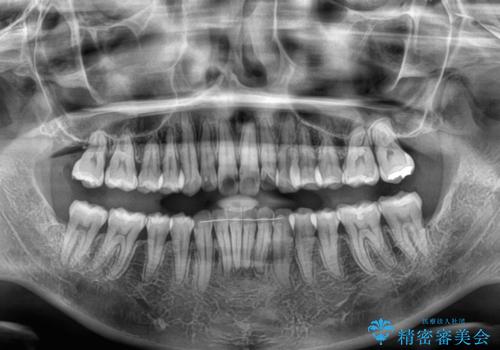

- デコボコと飛び出している前歯を気にして来院された患者様です。

歯列としてはインビザラインでもワイヤー矯正でも対応できるものでしたが、奥歯の咬み合わせを見た時に上顎がやや前方にあり、インビザライン単独では時間のかかってしまう可能性があるため、補助装置を治療当初に使用することで、インビザラインによる治療をスムーズに行えるように計画しました。